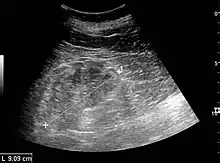

- Renal ultrasonography is useful for prognostic purposes in finding signs of chronic kidney disease, which however may be caused by many other diseases than glomerulonephritis.[10]